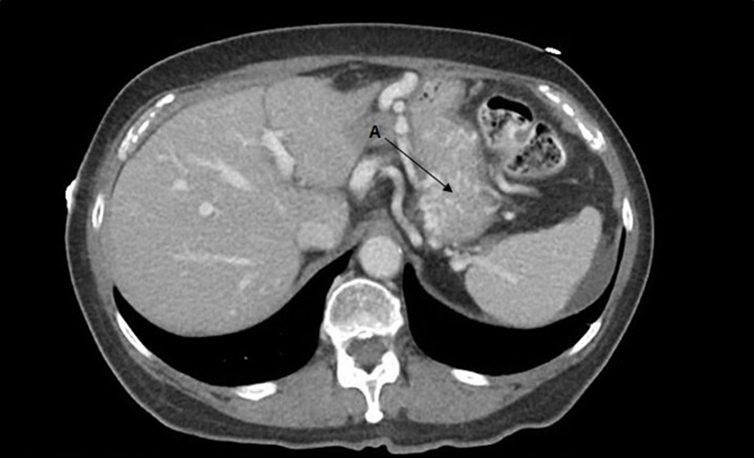

A 69 year old female with a history of pancreatic mucinous cystadenoma (treated with Whipple procedure) and recently presumed liver cirrhosis presented to the hospital with dizziness and melanotic stools. On presentation, she was hypotensive with a blood pressure of 85/50 mmHg and tachycardic with a heart rate of 115 beats per minute. Her physical exam was pertinent for pale skin, dry oral mucosa, and delayed capillary refill. Her complete blood count showed a hemoglobin level of 5.7 g/dL which was a significant drop from her baseline of 10 g/dL. Her liver functions tests and coagulation parameters were within normal limits. Computed tomography (CT) of the abdomen with contrast showed a mildly nodular liver and no signs of bleeding. She was resuscitated with blood transfusions and intravenous fluids. Her GI bleed was treated with octreotide and pantoprazole infusions. Gastroenterology specialists were consulted immediately. Patient was taken for an esophagogastroduodenoscopy (EGD) next morning which failed to find an active bleeding source but showed grade 2 gastric varices with significant gastric wall edema. Despite medical management, patient continued to have persistent symptoms. CT enterography also revealed prominent gastric varices and gastric body wall edema (Figure 1). Tagged

Figure 1.CT enterography showing gastric varices and gastric wall edema (A) .